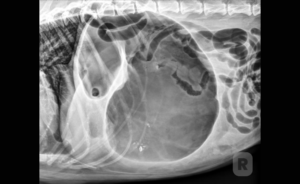

At the heart of the conference, within the sprawling 345,000 sq. ft. Exhibit Hall, the Vetpocket team found a dynamic platform to demonstrate how our products, especially our clinical companion app, are revolutionizing veterinary practice. Engaging directly with practitioners, technicians, and industry professionals, we shared insights into how our tools can enhance diagnostic accuracy, streamline patient management, and foster better client communication.